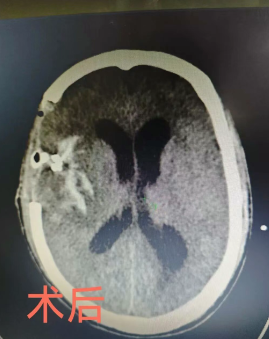

手术台上,挑战巨大。患者动脉瘤直径达约20毫米,并已破裂出血。在彭超博士的现场指导下,梁海波主任团队精细操作,在麻醉科的全程精准护航下,成功将动脉瘤完美夹闭,一举解除了再出血风险。术中面对脑组织肿胀的难题,团队果断并行去骨瓣减压术,有效保护了脑功能。目前,廖伯已恢复意识,正在重症医学科二区接受系统化的后续治疗与康复,病情稳步向好。